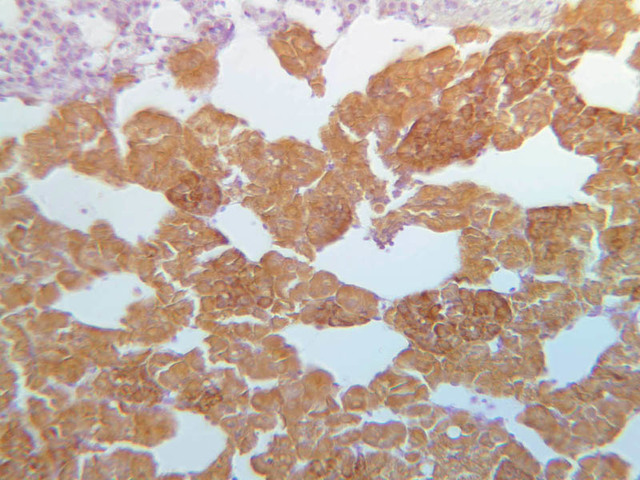

The neurohypophysis arises as an outpocketing of neuroectoderm from the floor of a portion of the brain called diencephalon. It is divisible into the pars nervosa, which forms the posterior portion of the main mass of the pituitary, and the infundibulum, or pituitary stalk. In H&E-stained sections, the neurohypophysis is distinctly eosinophilic. The adenohypophysis (anterior pituitary) has three different types of secretory cells, which are best visualized in the trichrome-stained preparation on slide B-65: (1) acidophils have a reddish staining cytoplasm, owing to the presence of secretory granules. These cells secrete growth hormone (GH) and prolactin (PRL); (2) basophils are slightly larger cells with bluish staining granules present in the cytoplasm. These cells tend to occur in small groups or clusters. Basophils are responsible for the production of thyroid stimulating hormone (TSH), adrenocorticotrophic hormone (ACTH), and the gonadotrophic hormones follicle stimulating hormone (FSH) and luteinizing hormone (LH ); (3) chromophobes or C cells are smaller cells and have only a small amount of poorly staining cytoplasm (B-63, H&E [2.5x-labeled, 10x, 20x, 40x-labeled] [2.5x, 10x, 20x, 40x-labeled]; B-65, trichrome [2.5x, 10x, 20x, 40x-labeled] [2.5x, 10x, 20x, 40x] [10x, 20x, 40x-labeled] [2.5x, 10x, 20x, 40x] [2.5x, 10x, 20x, 40x]). What is the target organ of each of the hormones produced by the adenohypophysis? Note the rich vascularity of the adenohypophysis. Can you describe the blood supply and its significance?

B63, Pituitary, 2.5x (H&E) B63, Pituitary, 10x Labeled (H&E) B63, Pituitary, 20x (H&E) B54, Pituitary, 2.5x (AF) B54, Pituitary, 10x (AF) B54, Pituitary, 20x (AF) B54, Pituitary, 40x (AF) B65, Pituitary, 2.5x (Trichrome) B63, Pituitary, 2.5x Labeled (H&E) B63, Pituitary, 10x (H&E) B63, Pituitary, 20x (H&E) B63, Pituitary, 40x Labeled (H&E) B63, Pituitary, 2.5x (H&E) B63, Pituitary, 10x (H&E) B63, Pituitary, 20x (H&E) B63, Pituitary, 40x Labeled (H&E) B65, Pituitary, 2.5x (Trichrome) B65, Pituitary, 10x (Trichrome) B65, Pituitary, 20x (Trichrome) B65, Pituitary, 40x Labeled (Trichrome) B65, Pituitary, 2.5x (Trichrome) B65, Pituitary, 10x (Trichrome) B65, Pituitary, 20x (Trichrome) B65, Pituitary, 40x (Trichrome) B65, Pituitary, 10x (Trichrome) B65, Pituitary, 20x (Trichrome) B65, Pituitary, 40x Labeled (Trichrome) B65, Pituitary, 2.5x (Trichrome) B65, Pituitary, 10x (Trichrome) B65, Pituitary, 20x (Trichrome) B65, Pituitary, 40x (Trichrome) B65, Pituitary, 2.5x (Trichrome) B65, Pituitary, 10x (Trichrome) B65, Pituitary, 20x (Trichrome) B65, Pituitary, 40x (Trichrome) B64, Pituitary, 2.5x (AF) B64, Pituitary, 10x (AF) B64, Pituitary, 20x (AF) B64, Pituitary, 40x (AF) B63, Pituitary, 2.5x (H&E) B63, Pituitary, 10x (H&E) B63, Pituitary, 20x (H&E) B63, Pituitary, 40x (H&E) B65, Pituitary, 2.5x Labeled (Trichrome) B65, Pituitary, 10x (Trichrome) B65, Pituitary, 20x (Trichrome) B65, Pituitary, 40x (Trichrome) B65, Pituitary, 2.5x Labeled (Trichrome) B65, Pituitary, 10x (Trichrome) B65, Pituitary, 20x (Trichrome) B65, Pituitary, 40x (Trichrome) B64, Pituitary, 2.5x (AF) B64, Pituitary, 10x (AF) B64, Pituitary, 20x (AF) B64, Pituitary, 40x Labeled (AF) B64, Pituitary, 2.5x (AF) B64, Pituitary, 10x (AF) B64, Pituitary, 20x Labeled (AF) B64, Pituitary, 40x (AF)